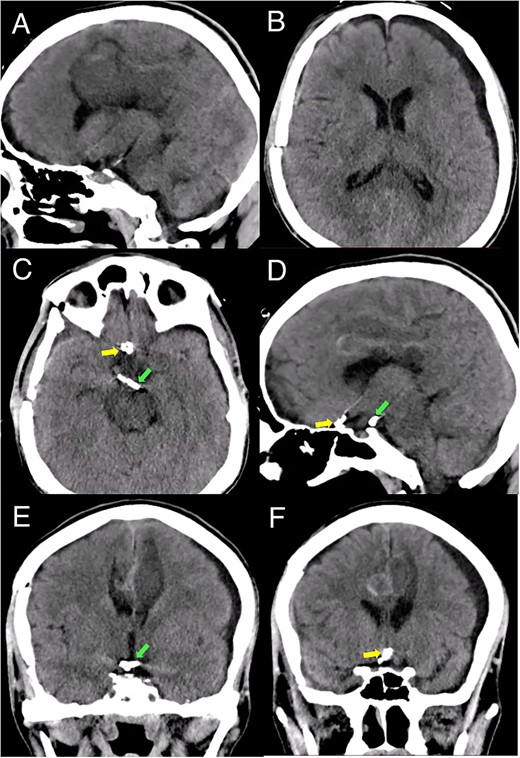

A multislice computed tomography (CT) without contrast revealed an extensive interhemispheric hematoma in the frontoparietal region, subarachnoid hemorrhage, and intraventricular hemorrhage in the adjacent area (Fisher grading score of IV) (Fig. 1). In addition, cerebral angiotomography and 3D reconstruction imaging suggested the presence of two abnormal vascular lesions: (i) a fusiform aneurysm of 12 × 7 mm in an accessory A2 portion of the ACA and (ii) an unruptured saccular aneurysm of 3.3 × 2.8 mm in the distal segment of the basilar artery adjacent to the anterolateral surface of the P1 segment and the left superior cerebellar artery (Figs 2 and 3).

Brain CT without contrast shows a large interhemispheric hematoma, intraventricular hemorrhage, and subarachnoid hemorrhage (white arrows) in (A) Sagittal, (B) Axial, and (C) Coronal views.